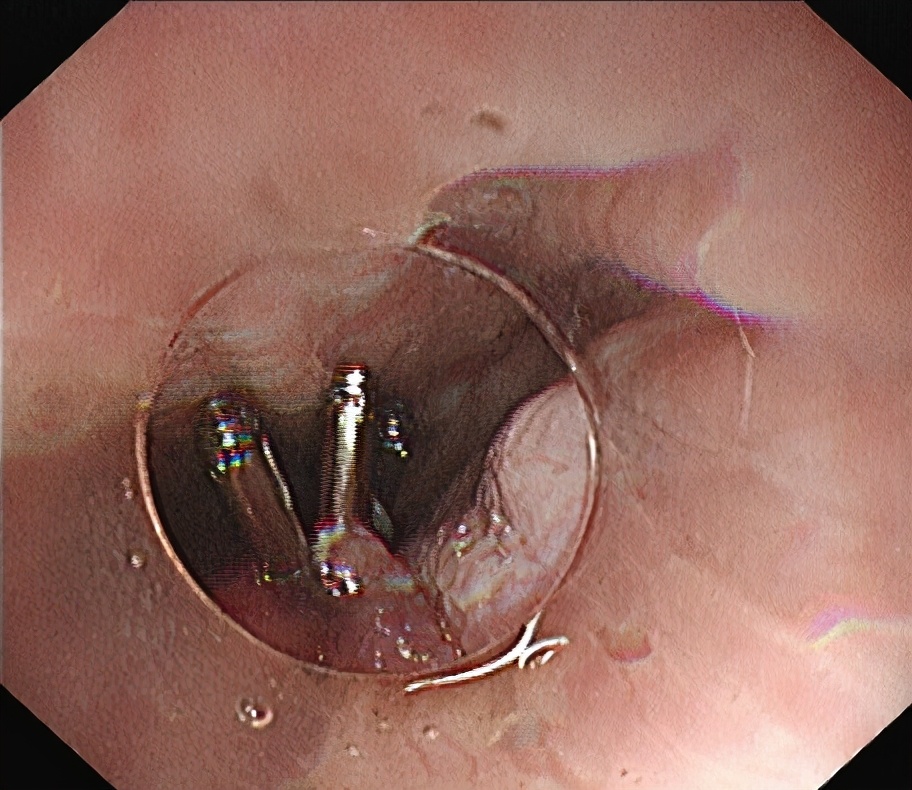

退出“隧道”前观察,钛夹关闭黏膜层切口。